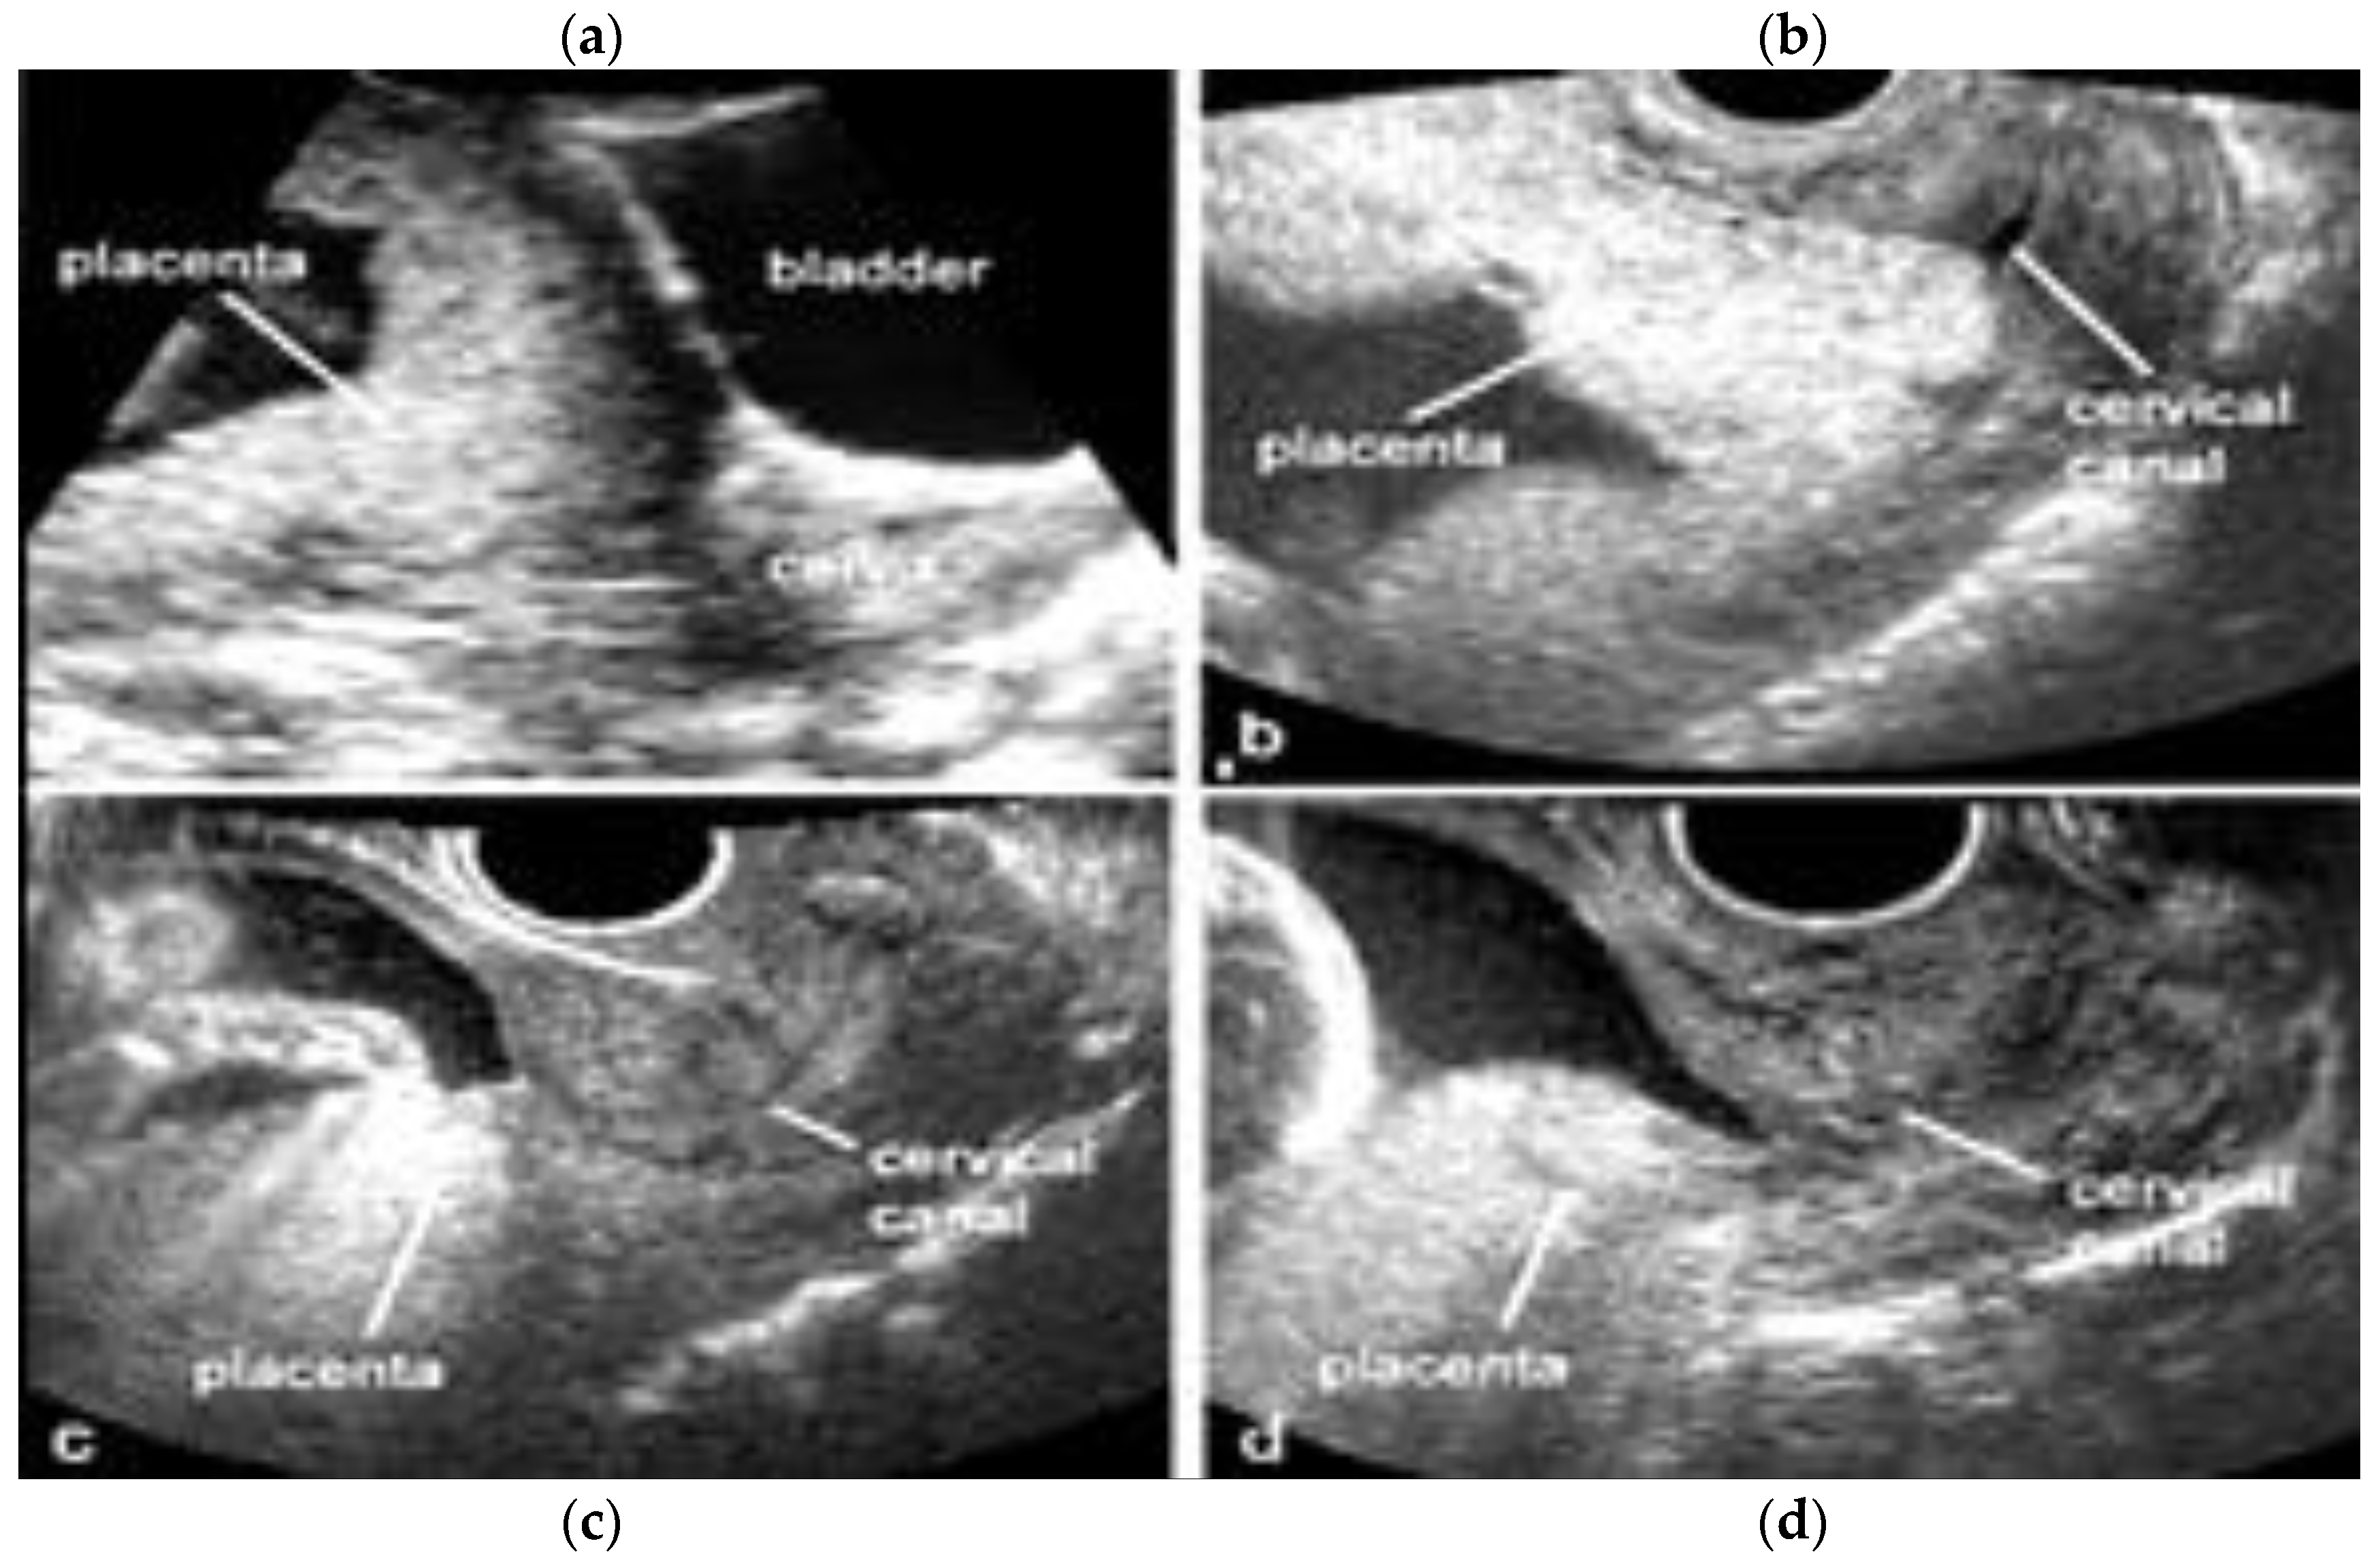

Placenta praevia is a condition in which the placenta develops within the lower uterine segment and overlies the cervix [7]. Previous terminology, such as symmetric or complete, has now been replaced and the condition is now classified as placenta praevia major [7,21,22] On the other hand, if the placenta does not overlie the cervix, but its edge is located within 2.0 cm of the cervical os, it is called a low-lying placenta. This type of placenta is now defined as placenta praevia minor [7,22]. The incidence of placenta praevia is seen in around 4 to 5 of 1,000 pregnancies, and the risk factors associated with this condition are advanced maternal age, multiparity, previous placenta praevia, chronic hypertension, diabetes mellitus, smoking during pregnancy, multiple gestation and assisted reproductive technology (ART) [22]. This placental anomaly, besides being one of the major risk factors for PAS, is associated with maternal bleeding, Cesarean section and prematurity [7,22,23]. The use of transvaginal ultrasound allows for the better definition of the placental anatomy in relation to the cervix with a sensitivity of 88% and specificity of 99% [22]. In the face of placenta praevia and low-lying placenta, the gray-scale third trimester ultrasound has a great negative predictive value in detecting cases of accretism when normal hypoechogenic space is seen between the uterus and placenta and through the lack of the visualization of placental lacunae [24]. Ultrasound has shown a low sensitivity in the diagnosis of PAS in mothers with posterior placenta praevia while MRI has superior accuracy and fewer false negative results, but higher accuracy was obtained through a combination of both techniques [23,25,26] (Figure 3 and Figure 4).

Figure 3.

Transvaginal two-dimensional ultrasound showing placenta praevia major (upper panel, a,b) and a placenta praevia minor (lower panel, c,d).

Figure 4.

Fetal MRI (sagittal T2) performed at 30 weeks and 26 week’s gestation in two different fetuses (A,B), demonstrating a placenta praevia major and accretism. (Legend: Pl: placenta; Cx: cervix).